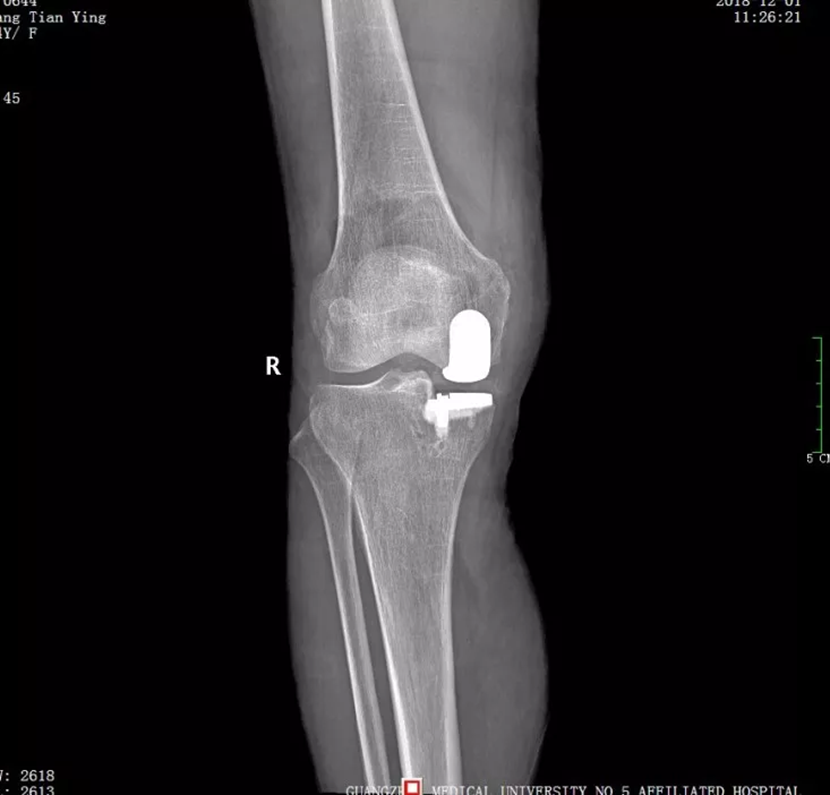

陈为坚主任对患者进行了仔细检查,发现她的左膝关节内翻畸形,也就是百姓常说的“罗圈腿”,一按压关节内侧就明显疼痛。X 光片、核磁共振报告左膝关节内侧软骨明显磨损,关节间隙明显变窄,被诊断为骨性关节炎。像这样的病情,以往一般会采取全膝关节置换手术治疗,但这需要对整个膝关节的关节面进行截骨,切除过多正常的骨质、交叉韧带和外侧半月板,损伤比较大。

陈为坚主任仔细研究患者的实际病情,最终制定了微创下膝关节单髁置换的手术方案。随后,陈为坚主任为患者实施手术,术中切除膝关节内侧已经磨损和破坏的软骨表面,用人工假体进行置换,用骨水泥进行固定。仅仅两个小时,手术就顺利完成。术后第二天王阿姨即可下地行走,疼痛大大减轻。“真是感谢医生,我这一下算是脱胎换骨了。”王阿姨说。

膝关节单髁置换是相对全膝关节置换而言的一种新型微创手术,简单讲就是“哪里坏了换哪里”。陈为坚主任介绍,人体的膝关节包含内侧胫股间室、外侧胫股间室、髌股间室3个间室。如果3个间室都有不同程度的磨损,疼痛影响了日常生活就需要行全膝关节置换。传统的膝关节置换,是对全膝关节的整体置换。如果只有1个间室磨损较大,其他两个间室良好,那么,膝关节单髁置换术就是这类患者的有效手段,通过微创化、精准化的手术操作,仅对单一磨损严重的间室进行更换,在磨损的关节面上加上“保护套”,不影响其他间室的正常功能。